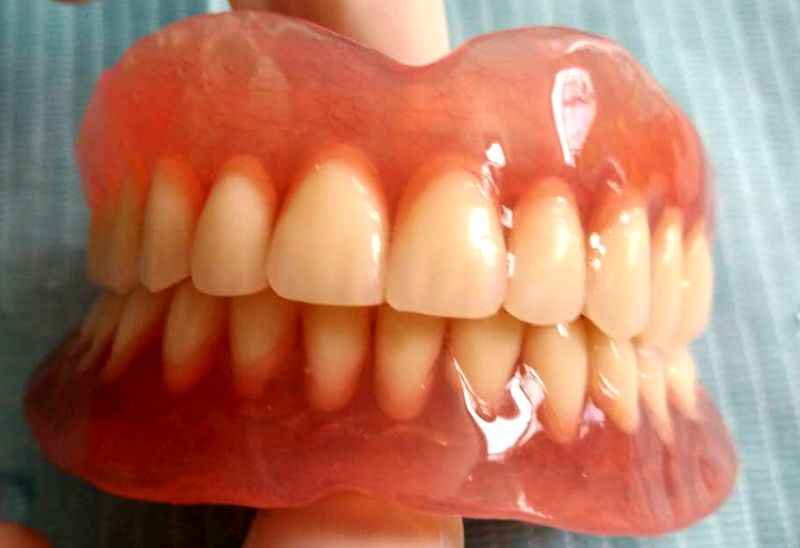

义齿正面,尚未戴入口腔

义齿反面,可以看到与种植体的基桩连接的小帽